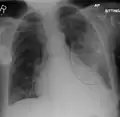

A chest X-ray showing a very prominent wedge-shape bacterial pneumonia in the right lung